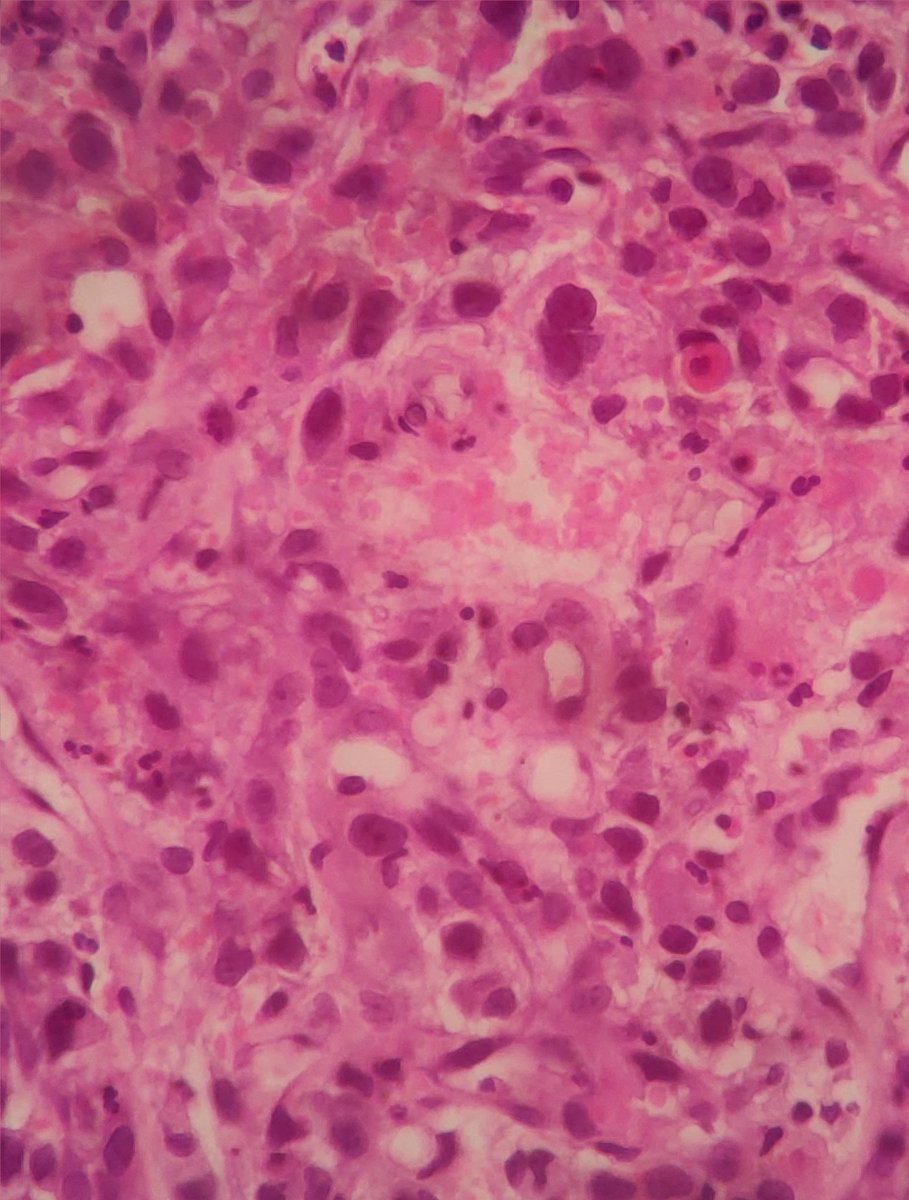

Spotted this wretched tumour in the endometrium of a poor 60 year old lady #pathology #twitterpath #gynaecpathology

docnax's tweet image. Spotted this wretched tumour in the endometrium of a poor 60 year old lady #pathology #twitterpath #gynaecpathology